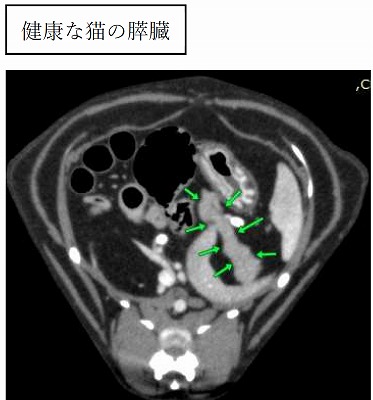

健康な猫ちゃんの膵臓ははっきりとして白い実質なのに比べ、棉花糖ちゃんでは膵臓のまわりにモヤモヤとした「毛羽立ち」のようなものが見えます。これは膵臓に激しい炎症や壊死が起こった場合に認められます。

CT検査の結果、膵炎による総胆管の閉塞が疑われました。

膵炎が起こると膵臓が腫れてしまい、膵臓の近くにある総胆管の出口を塞いでしまいます。結果として胆汁が詰まり、黄疸が起こります。